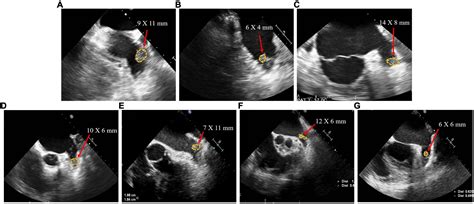

The most common method for the closure of left atrial appendage is a catheter-based, minimally invasive approach. During the procedure, the patient is placed under general anesthesia. The cardiologist inserts a small tube, or sheath, into a vein in the groin and guides it up to the heart. Using specialized imaging—often a combination of fluoroscopy and transesophageal echocardiography (TEE)—the device is deployed to seal the opening of the appendage.